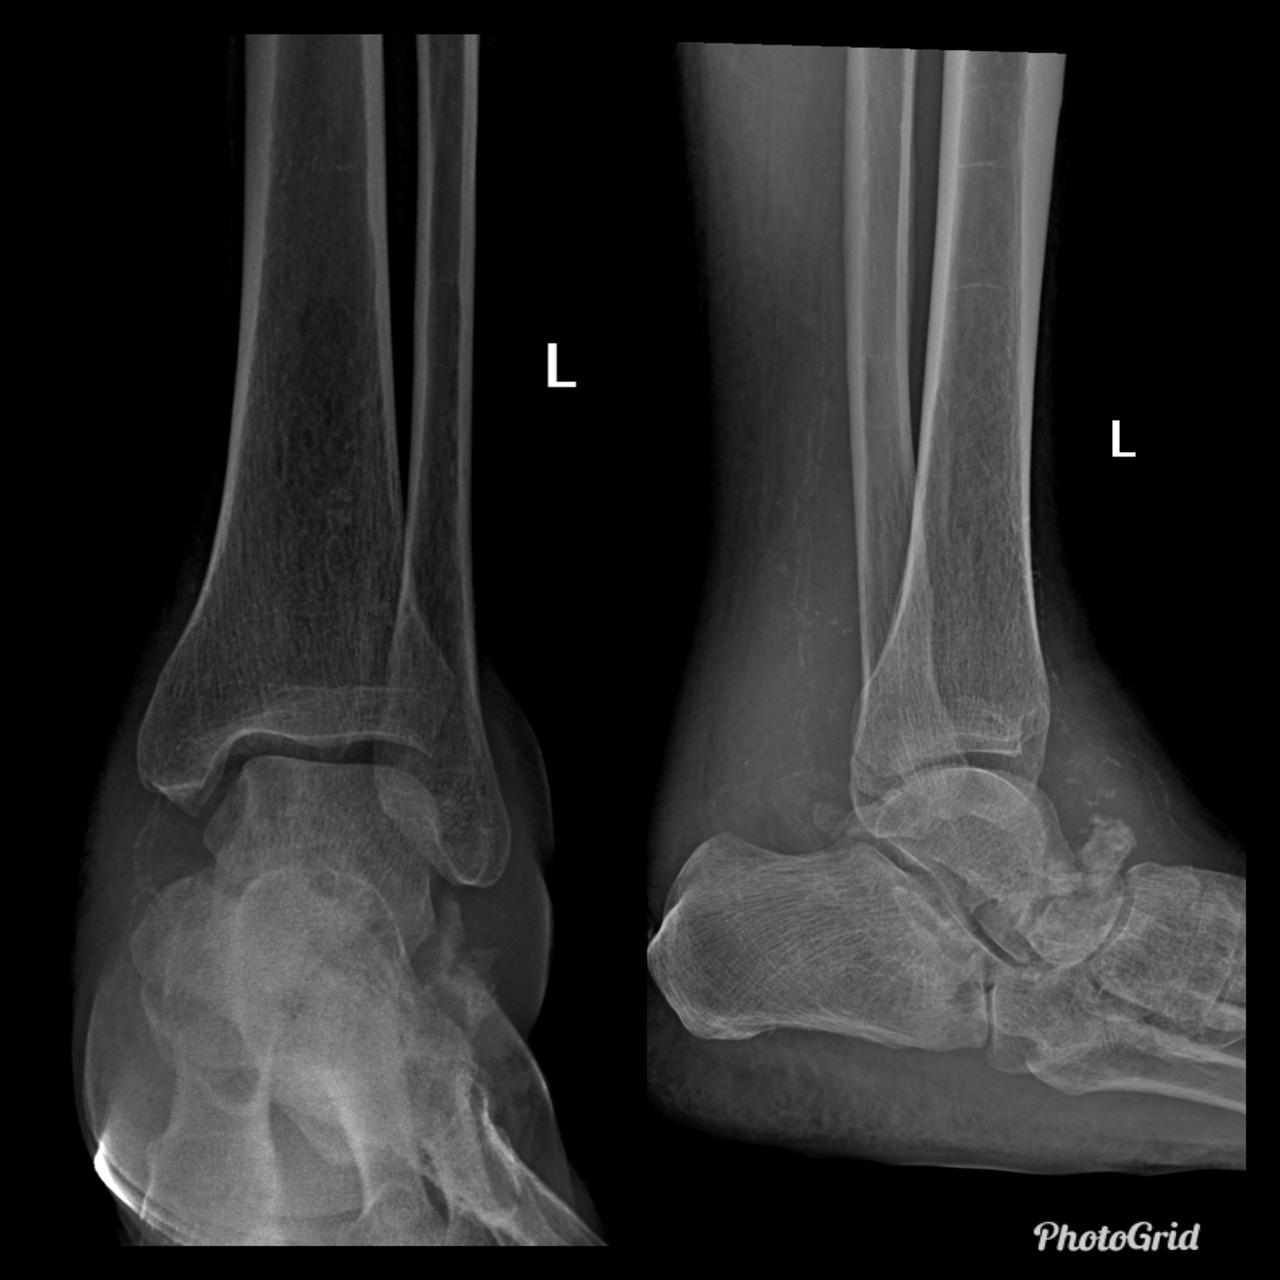

In the presented case there are destruction of talar head and neck with dislocation of talo-navicular joint, resorption of midfoot bones, subchondral sclerosis and multiple subchondral cysts on talocalcaneal aspect and cuboid facet of the calcaneum, progressive decrease of calcaneal inclination with typical rocker-bottom deformity, soft tissue swelling and arterial calcification. Bony debris are seen on dorsal aspect of the foot and posterior ankle joint. All findings are suggestive of Charcot neuro-osteoarthopathy, which is primarily an articular disease and most commonly located in the midfoot.